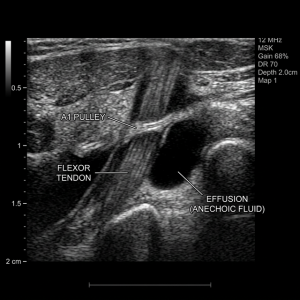

2. Ultrasound Guidance: We use advanced, real-time imaging to ensure the hydrogel is injected with 100% precision directly into the correct joint space.